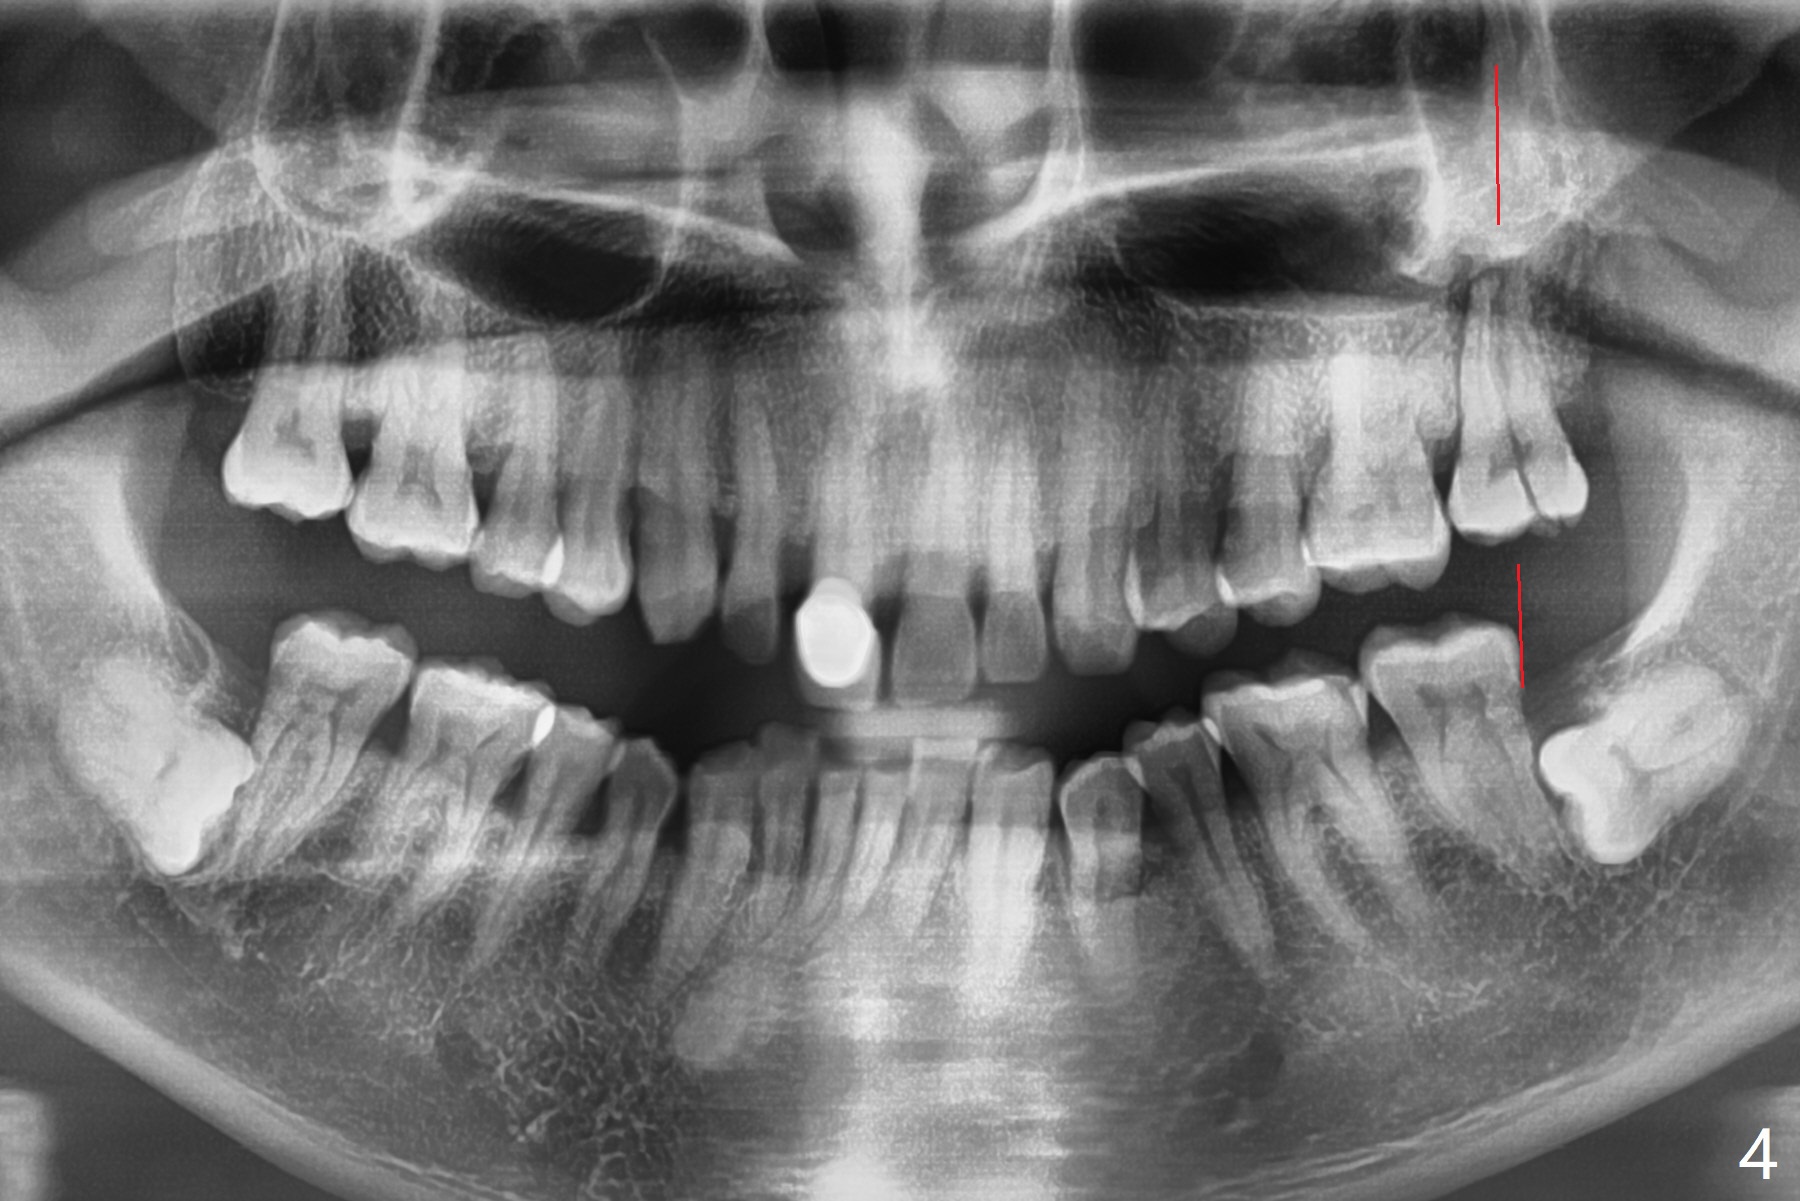

A 44-year-old man presented to clinic with pain of the upper left quadrant (Fig.1), but the affected tooth was not determined until 5 months later (Fig.3,4). Retrospectively the minor crack is visible earlier (Fig.2 arrowheads). It appears that the remaining bone (sinus floor) is limited (Fig.5). Magic Sinus lift or Magic Expanders will be used for sinus lift. Prepare 2-3 pieces of PRF membranes: one or two for sinus lift; the third one to close the socket if primary stability is <30 Ncm.